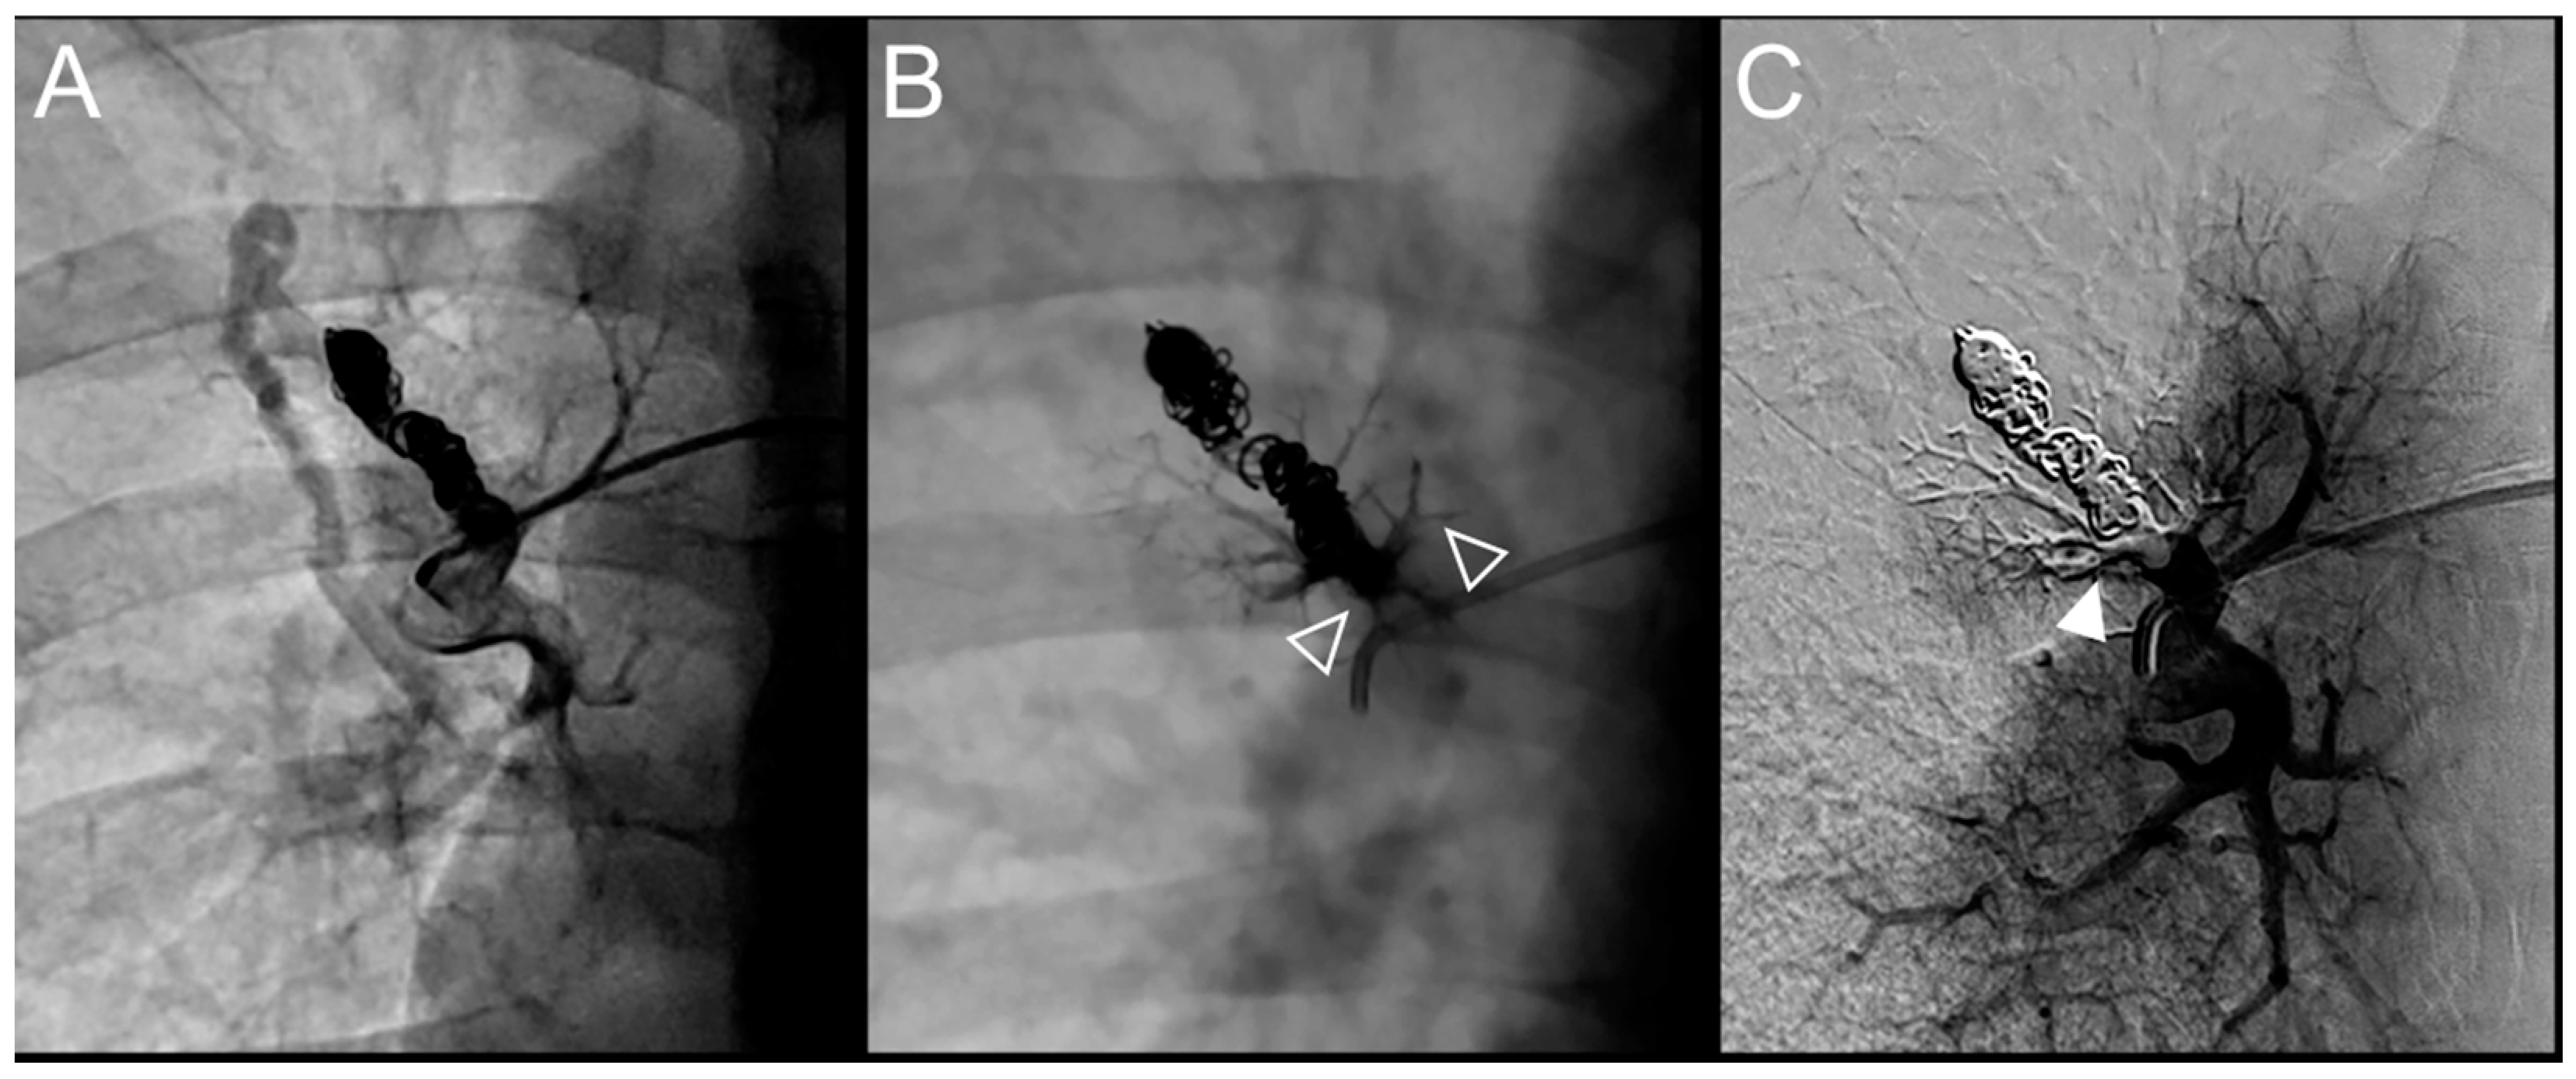

Figure 5.

Case example of a 37-year-old woman treated for a simple recurrent pulmonary arteriovenous malformation in the lower right lobe. Embolization was performed using Onyx® (0.5 mL) to fill the afferent artery within the pre-implanted coils and resulted in an immediate complete occlusion, maintained at 34 months follow-up. No leak in the aneurysm or in the vein was reported, but a leak in the upstream sub-segmental arteries was identified. (A). Opacification of the afferent artery showed a recanalization through existing coiling. (B). Opacity within and upstream of the pre-implanted coils (empty arrowheads) showed the distribution of Onyx®, with a leak in a proximal arterial branch. (C). Opacification of the afferent artery showed the absence of opacification of the aneurysmal sac and the efferent vein in favor of immediate occlusion. An altered opacification in the upstream branch (full arrowhead) was identified due to the leak of Onyx®. (D). The one-year follow-up chest CT showed a distal lung infarction related to embolization. Of note, the patient did not suffer from chest pain or pleural effusion after the embolization procedure.

Figure 6.

Case example of a 35-year-old man treated for a recurrent simple pulmonary arteriovenous malformation in the right lower lobe. The pulmonary angiograph showed a distance between the last coil and a healthy arterial branch too short to add additional coils. Embolization was thus performed using Onyx® (0.4 mL) to fill the afferent artery upstream and in the pre-implanted coils, without any leak neither in the aneurysm nor in the vein. It resulted in an immediate complete occlusion until 46 months after the procedure when a recurrence was reported. (A). Opacification of the afferent artery of a PAVM in the lower right lobe showing a recanalization through the pre-implanted coils. (B). Opacity in and upstream (empty arrowheads) the coils showing the distribution of the Onyx®, without any evidence of a leak in the aneurysmal sac, but with a leak in the small arterial branches. (C). Opacification of the afferent artery showing the absence of opacification of the aneurysmal sac and the efferent vein in favor of immediate occlusion. A perfusion defect was identified in a sub-segmental territory (full head arrow), not related to a symptomatic lung infarction.